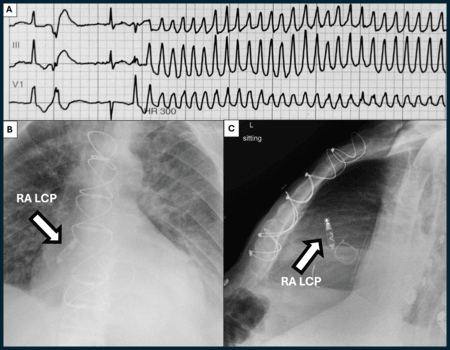

A 69-year-old patient with fungal bioprosthetic aortic valve endocarditis developed sustained VT, for which he was successfully resuscitated. He was prescribed a secondary prevention wearable defibrillator lifevest on discharge, but over a 2-week period the patient received 6 appropriate shocks by his wearable defibrillator for polymorphic and monomorphic VT episodes despite treatment with multiple anti-arrhythmic agents. In-patient telemetry identified S-L-S sequence preceding the VT episodes. Subsequently, a single chamber right atrial leadless pacemaker was placed and programmed to pace at eighty beats per minute. At 8 weeks post-implant, he experienced no further VT episodes (non-sustained or sustained).